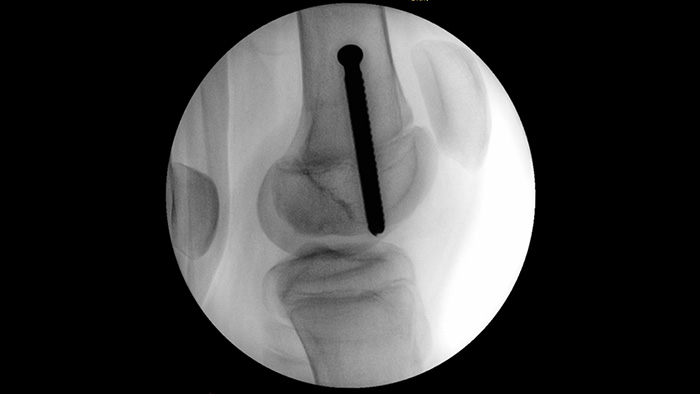

O MetalSmart exclui automaticamente artefactos metálicos causados por implantes metálicos para fornecer maior qualidade de imagem e controlo eficiente da dose durante procedimentos ortopédicos e pacientes com implantes metálicos, em comparação com sistemas sem exclusão de metais. O BodySmart promove a imagiologia e a eficiência da dose corretas à primeira, adaptando automaticamente o campo de medição à área de interesse.